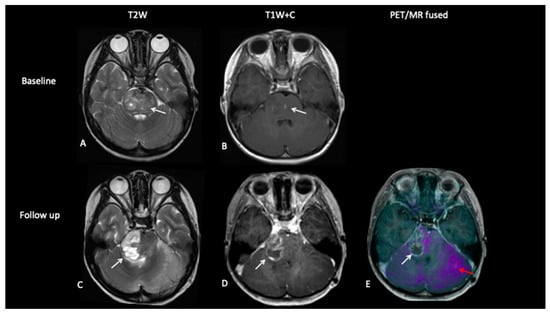

- Patient 3: Tumour Progression Versus Pseudoprogression

A 5-year-old female with diffuse midline glioma (DMG) presented with a short history of headaches, difficulty in walking and double vision. Radiology at diagnosis was consistent with diffuse intrinsic pontine glioma (DIPG). She commenced on 6 week course of focal radiotherapy (RT) to the pontine tumour with good initial response (Figure 6). The patient then went to Mexico for a form of targeted treatment and after four cycles developed clinical signs of disease progression. Whilst follow-up MRI demonstrated increased enhancement and raised the possibility of pseudoprogression, FDOPA PET demonstrated areas of avidity confirming clear progression.

Figure 6.

Baseline imaging demonstrates large pontine tumour (A) with focus of enhancement (B). Follow-up imaging demonstrated a large heterogenous right hemipontine mass (C,D) suspicious for tumour progression, but FDOPA (E) did not show increased uptake (white arrow) and was suggestive of pseudoprogression. However, FDOPA did show increased avidity in the left cerebellar hemisphere (red arrow) confirming non-enhancing tumour progression at that site.